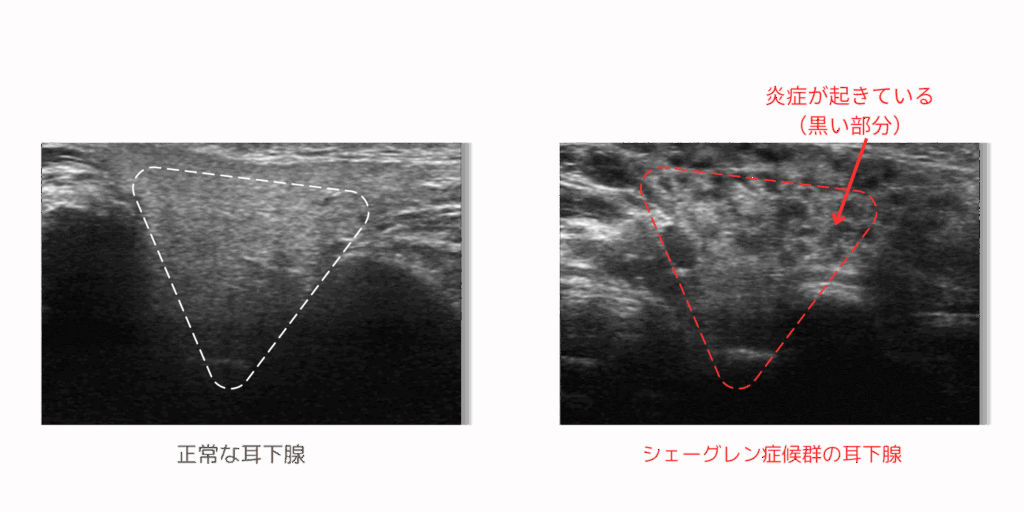

シェーグレン症候群ドック

シェーグレン症候群は女性に多いです(男性の約17倍)。唾液などの体液が減少することによる症状が生じます。そのため、発症すると「最近なぜか虫歯ができやすい」「よく口が渇く、よく目が乾く」というような症状が現れます。

唾液腺の状態をエコーで評価することで、異常を早期に発見することが可能です。また、唾液腺に生じる腫瘍についても早期発見につなげることが可能です。

| 検査の種類 | 検査内容 | ||

| 理学的検査 | 問診(既往歴・業務歴)、医師診察 | ||

| 血液検査 | 抗核抗体、抗Ro/SS-A抗体、抗La/SS-B抗体、抗セントロメア抗体、RF | ||

| 画像検査 | 唾液腺エコー |